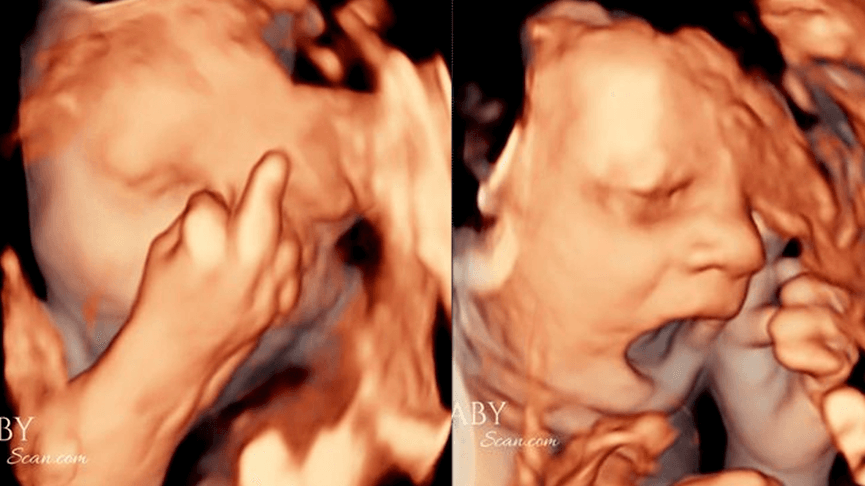

Bebê choca pais ao mostrar ‘dedo do meio’ e bocejar em ultrassom

O ultrassom em 4D registra o bebê “bocejando”, como se estivesse com sono, e mostrando o “dedo do meio”.